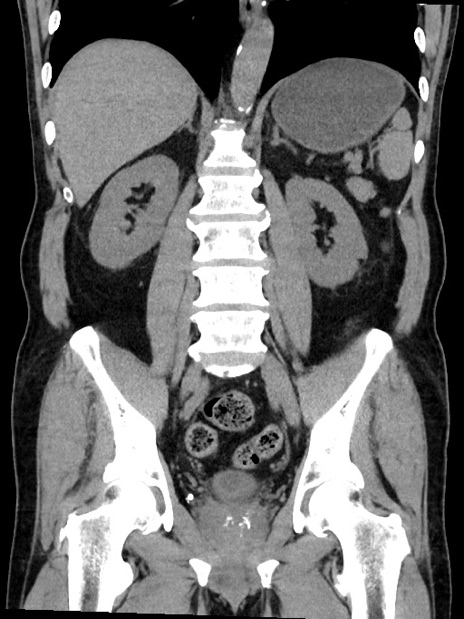

症例35(冠状断像)

【症例】70歳代 男性

【主訴】腹部膨満、嘔吐

【現病歴】昨日より腹部膨満感出現。本日増悪し、仙痛出現。嘔吐あり、受診。

【既往歴】糖尿病、胆摘後

【身体所見】BP 149/80mmHg、HR 74/min、BT 35.9℃、腹部:膨満、軟、圧痛なし。腸雑音減弱あり。上腹部正中切開瘢痕あり。

【データ】WBC 13500、CRP 1.72